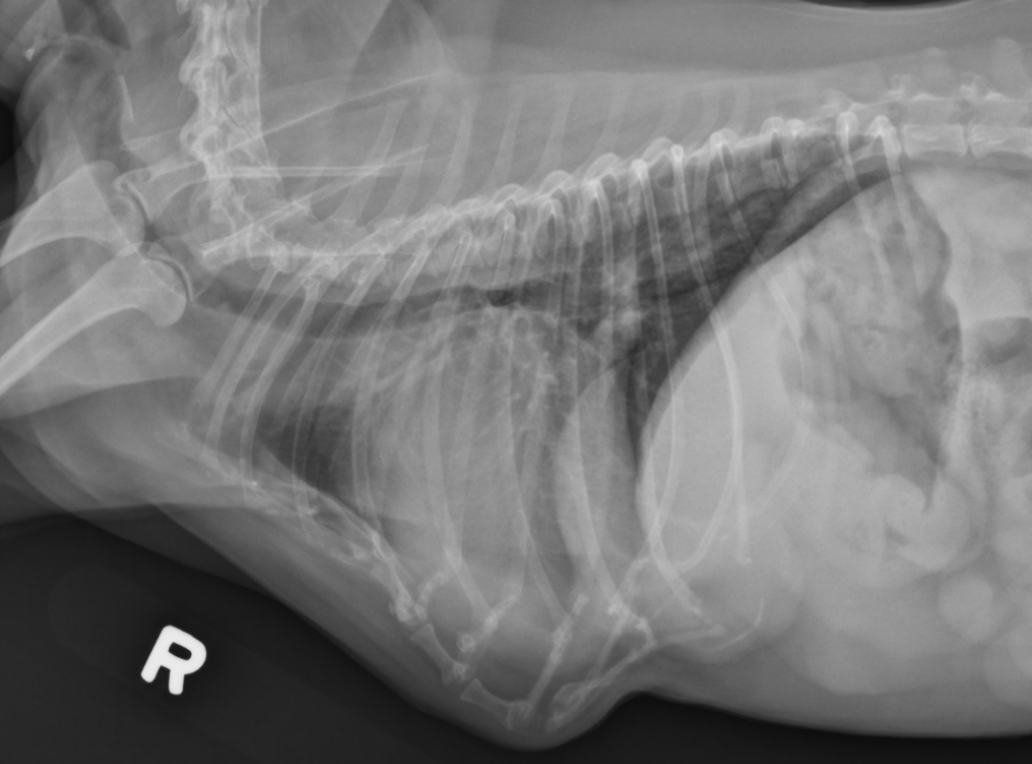

What is shown in these images?

acquired (traumatic) diaphragmatic hernia

-abnormal soft tissue content in thoracic cavity

-no diaphragm outline noted

-shifted gastric axis